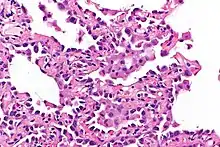

Micrograph showing multifocal micronodular pneumocyte hyperplasia. H&E stain.

- Well-demarcated, nodular lesions ranging 2–5 mm in pulmonary parenchyma.

- Type II pneumocytes without nuclear atypia lined thickened alveolar septa and proliferated papillary structures.

- Enlarged cuboidal cells lining mildly thickened alveolar septa.[11]

- Enlarged cuboidal cells have abundant, eosinophilic cytoplasm and large, round nuclei.[12]

- Papillary pattern with irregular margin and lymphocyte infiltration in the stroma.[13]

- No proliferation of immature smooth muscle cells suggestive of lymphangioleiomyomatosis.